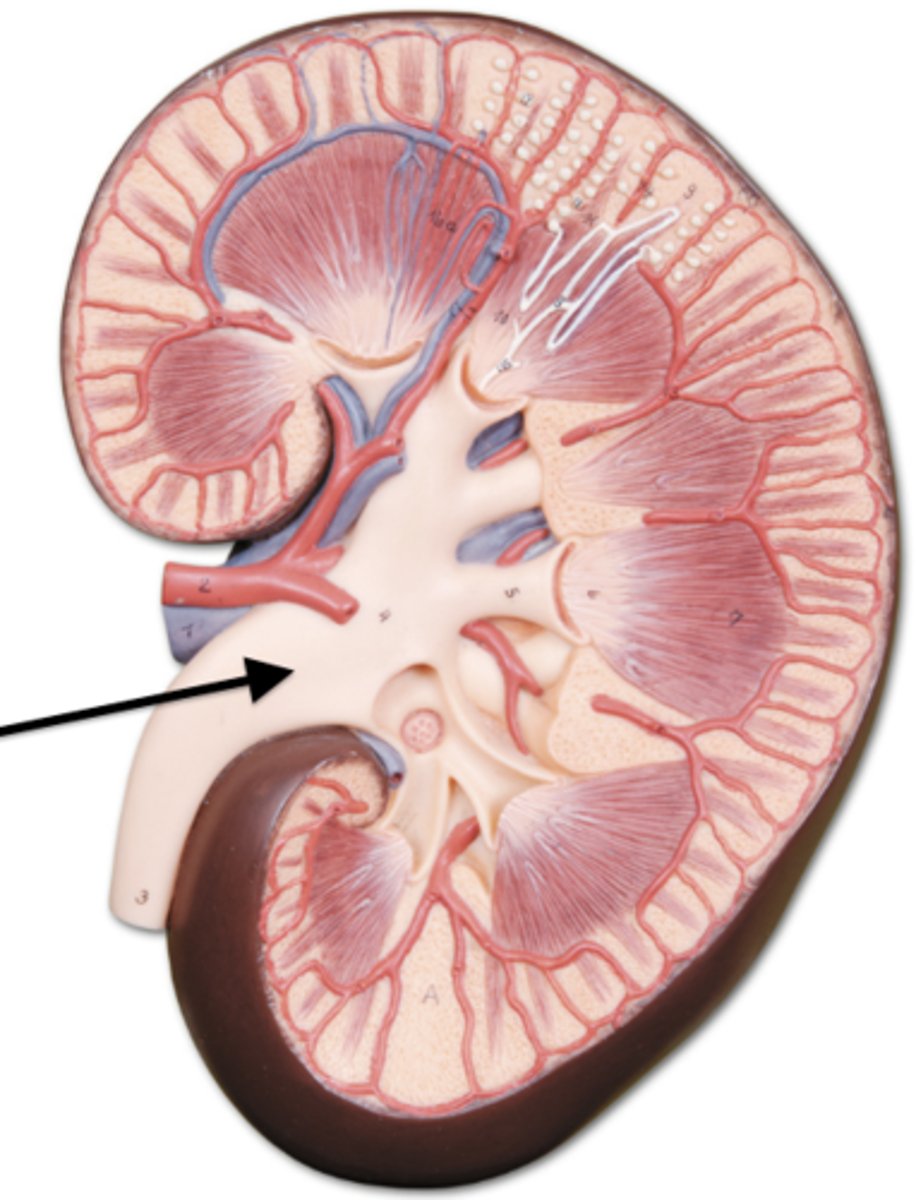

kidney

fibrous capsule

outer covering

renal cortex

renal medulla

renal papilla

major calyx

minor calyx

renal pelvis

renal pyramids

renal columns

renal artery

renal vein